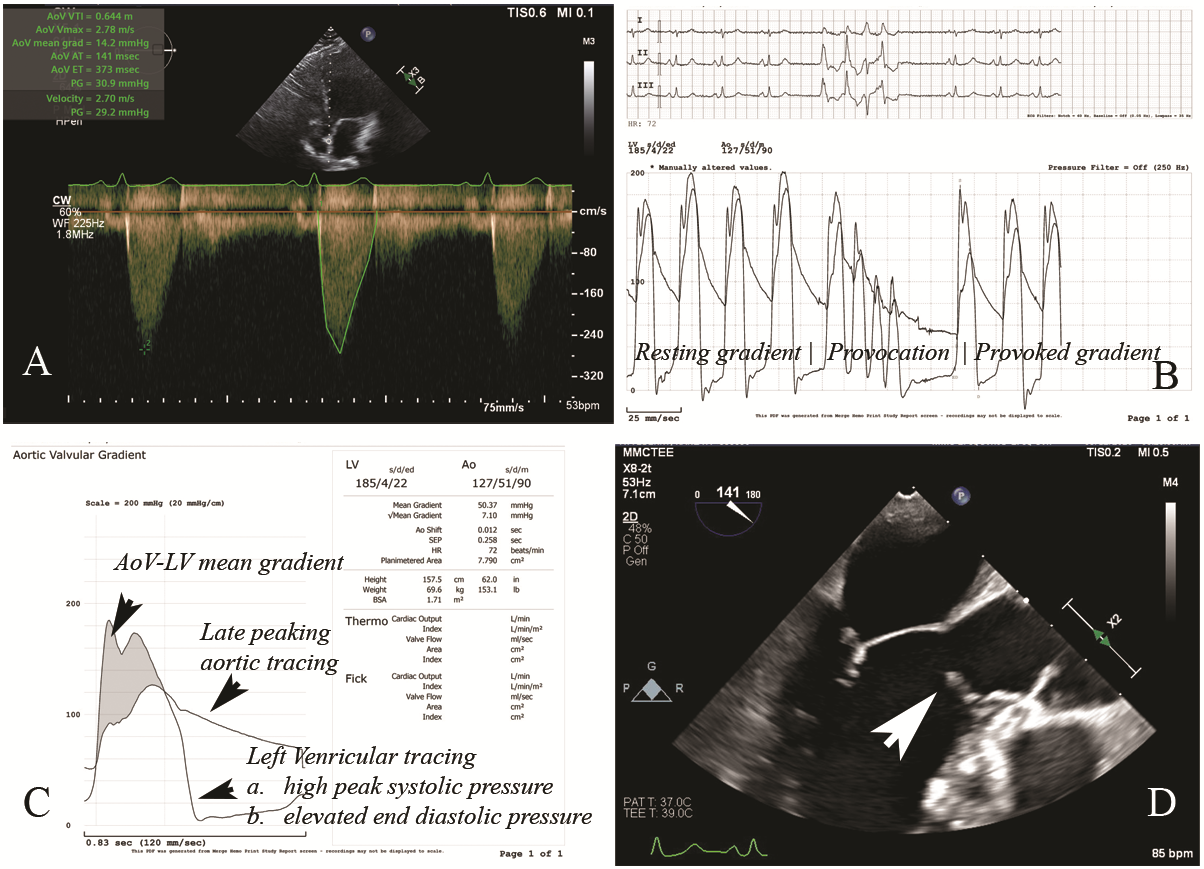

A 42-year-old woman who underwent subaortic membrane surgical resection in 2014 presented with severe dyspnea and recent syncope. Evaluation in the emergency room revealed stable vital signs and unremarkable electrocardiogram and cardiac biomarkers. Transthoracic echocardiogram showed an aortic valve (AoV) peak velocity of 2.78 m/s, a peak gradient (PG) of 31 mm Hg, a mean gradient of 14 mm Hg, and an AoV area of 2.09 cm² (Figure A). There were elevated pressure gradients across the LVOT and AoV, with a PG of 31 mm Hg at rest.

Regrowth of subaortic membrane was suspected given the normal AoV morphology and elevated gradients. Cardiac catheterization demonstrated normal coronary arteries, but an elevated left ventricular end-diastolic pressure at 30 mm Hg. Resting and provoked LVOT gradient were elevated at 20 and 50 mm Hg, respectively (Figure B and C). Transesophageal echocardiogram (TEE) revealed regrowth of subaortic membrane in the LVOT (Figure D). Video 1 shows the mid-esophageal long-axis view through the LVOT and aortic valve. Additionally, Video 2 shows the mid-esophageal long-axis view through the LVOT and aortic valve; X-plane focused at the subaortic membrane and color flow Doppler is shown in Video 3.